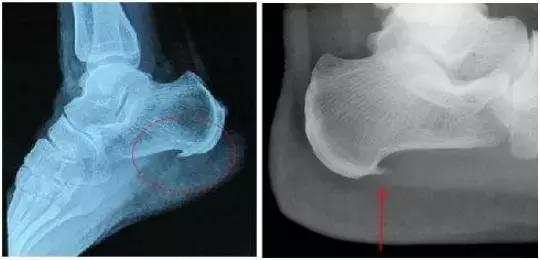

(2)跟骨骨折

对于正常人来说,跟骨是不容易骨折的。但若从高处坠落,或骨质流失严重人群的跟骨的确易骨折。若脚后跟疼痛的同时,还出现肿胀、皮肤淤紫甚至不能行走的情况,这种可能性很大。

此时要立即到骨科就诊。医生会通过X片等检查明确是不是骨折,如果确实有骨折,就需要石膏固定或者手术治疗。